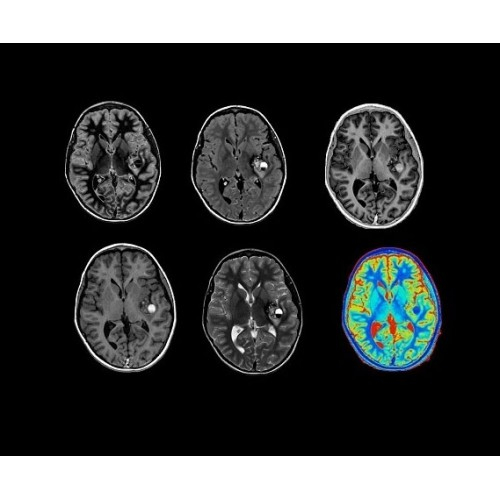

Стандартный пакет приложений SIGNA Works позволит вам достичь желаемых результатов в клинической практике благодаря набору высокоэффективных средств визуализации. Программные приложения, входящие в состав данных клинических пакетов, включают широкий спектр контрастов, функции обработки 2D- и 3D-данных, а также возможность коррекции артефактов движения. SIGNA Works предоставляет набор инструментов, необходимых для проведения эффективного клинического исследования.

Выведите клиническую практику на новый уровень — выходите за рамки стандартов благодаря инновационным приложениям SIGNA Works. Улучшенное качество изображений, повышенная эффективность и оптимизированный рабочий процесс помогут вам сканировать, как никогда прежде.

• ImageWorks — повысит производительность МРТ благодаря визуализации высокого качества с MAGIC, четкими результатами пост-процессинга с READYView.